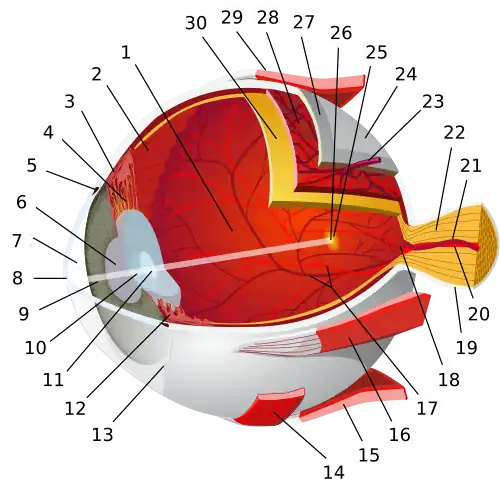

Medicine has been practiced since prehistoric times, and for most of this time it was an art (an area of creativity and skill), frequently having connections to the religious and philosophical beliefs of local culture. For example, a medicine man would apply herbs and say prayers for healing, or an ancient philosopher and physician would apply bloodletting according to the theories of humorism. In recent centuries, since the advent of modern science, most medicine has become a combination of art and science (both basic and applied, under the umbrella of medical science). For example, while stitching technique for sutures is an art learned through practice, knowledge of what happens at the cellular and molecular level in the tissues being stitched arises through science.

Selected image –

General images –

Anatomy - Biological engineering